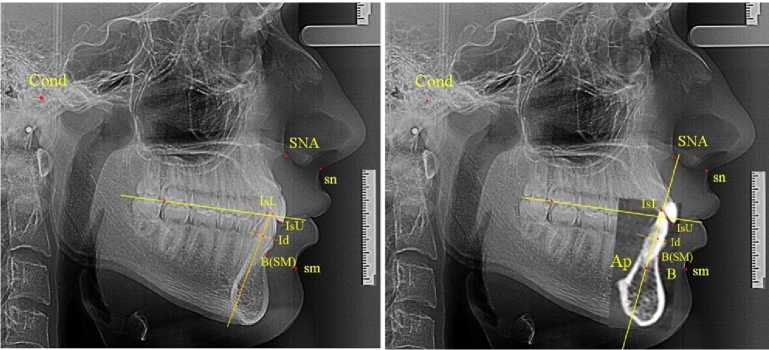

В результате анализа ТРГ пациентов с аномалиями окклюзии в вертикальном направлении было отмечено, что при вертикальной резцовой дизокклюзии величина угла гнатической части лица превышала 22° и составляла в среднем (27,78 ± 2,62)°. При глубокой резцовой окклю-зии/дизокклюзии величина угла гнатической части была менее 18° и составляла в среднем (15,84 ± 1,76)°.

Тем не менее построение апикально-кондилярного угла величиной в 5° определяла положение нижней апикальной точки Ар и проекцию верхушки корня В по Schwarz на кость на телерентгенограмме (рис. 4).

б

Рис. 4. Особенности углов т положения апикальной точки на ТРГ при вертикальной резцовой дизокклюзии (а) и глубокой резцовой окклюзии (б)

Кроме того, проведенный анализ положения резцов относительно окклюзионной линии позволил диагностировать положение резцов верхней и нижней челюсти и определять тактику лечения. При этом использовалась методика построения суставного круга, радиус которого составлял 2/3 от кондилярно-спинального расстояния (Cond-SNA). Точка пересечения перпендикуляра от середины линии Cond-SNA с контуром суставного круга определяло положение молярной окклюзионной точки. Высота молярного перпендикуляра служила ориентиром для определения передней и зад- ней точки с использованием коэффициента 1,2. Соединение передней, молярной и задней окклюзионных точек определяло положение окклюзионной линии.